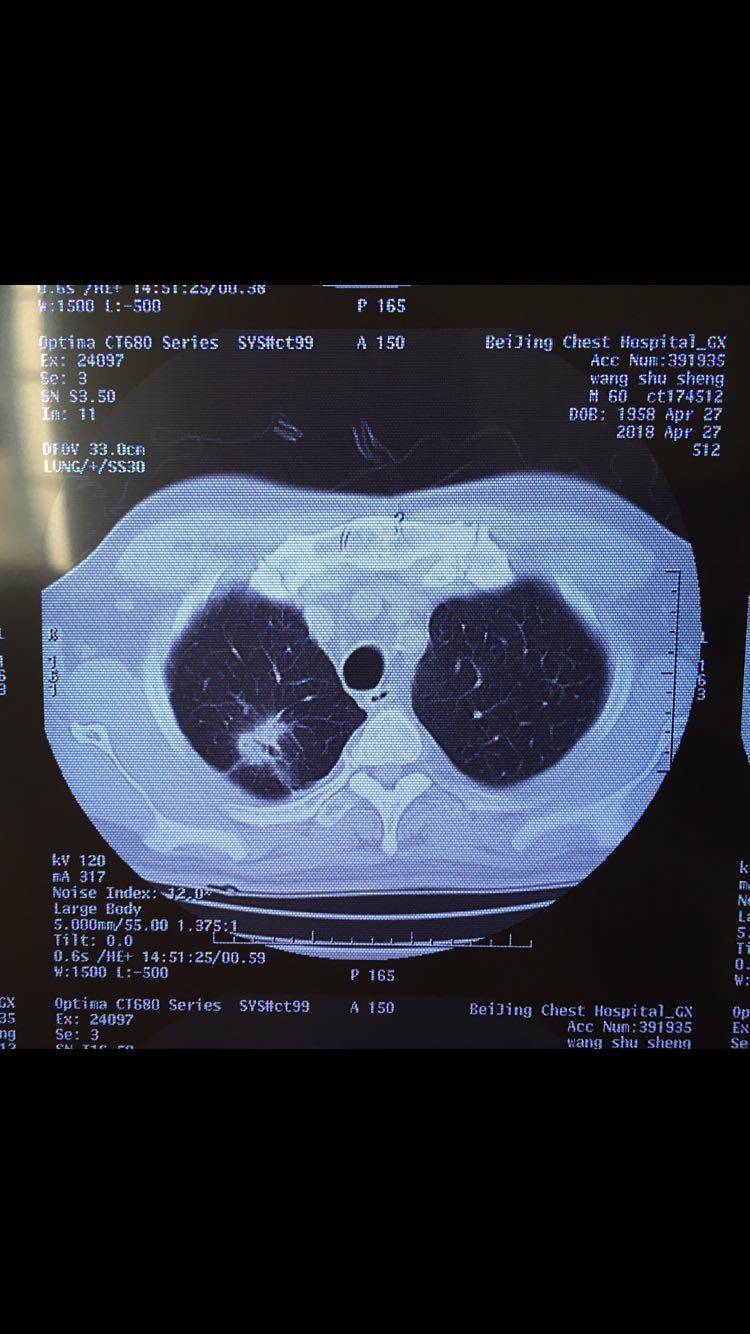

各位病友大家好,相求助听取一下大家的建议,目前患者情况很好,患者自今年三月起确诊肺腺癌晚期,目前使用贝伐珠单抗 培美曲塞 奈达铂化疗了5次,这周准备化疗第6次,主治医说想这次加上放疗同步治疗,我很犹豫,不知道如何选择。请大家给予治疗建议。患者基因检测没有靶向药。B超结果没有其他异常。这几次化疗后CT结果有病灶变小。

陈波医生放疗我也认为可以做的,但我觉得不需要同步放化疗,副作用大。化疗满6周期后,空窗一段放疗,用精准放疗去打击上肺的病灶